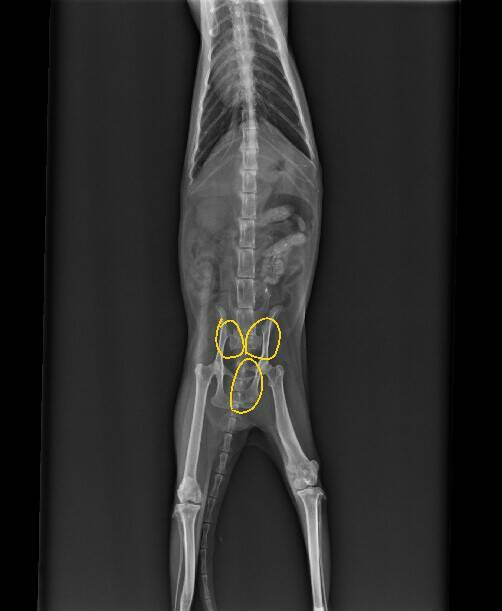

當下的小黑幾乎沒有抵抗的力氣,應該是多天沒吃飯造成的,趕緊送醫後,發現有嚴重貧血•腎衰•以及嚴重的骨盆骨折.......

聽到檢查結果,愛媽快要嚇傻了。因為血檢結果貧血很嚴重,先處理這部分,等身體狀況好些後再處理接下來的問題。動物近況說明: 經過了半個月的治療,小黑狀況有較穩定,但沒很大的起色。

醫師考慮小黑年事已高,血檢指數不好,手術風險太高了。後續就由愛媽帶回家裡繼續照護,希望小黑乖乖,不要兇人,能早日體會當一隻家貓也是不錯的事喔~